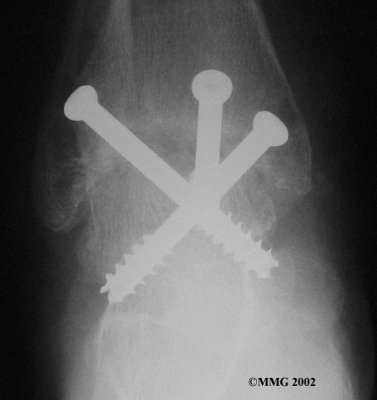

It is important when the surfaces are removed that the angles of the cut surfaces are correct. When the tibia is brought against the talus, the foot should be at a right angle to the lower leg. Once the cuts are made the bones must be held in place while they fuse. This can be done using large metal screws and metal plates if necessary. The screws are usually under the skin and are not removed unless they begin to rub and cause pain.

Inserting the screws

After ankle fusion, the physical therapists at FYZICAL Lubbock Southwest can help you learn to walk smoothly and without a limp. Although time needed for recovery varies among patients, an ankle brace will typically replace your cast after eight to 12 weeks. Your surgeon will take X-rays frequently to see if the bones are fusing together. You will probably need to use crutches during the time you wear the cast. As the fusion grows stronger, you will begin to put more weight on your foot when walking.